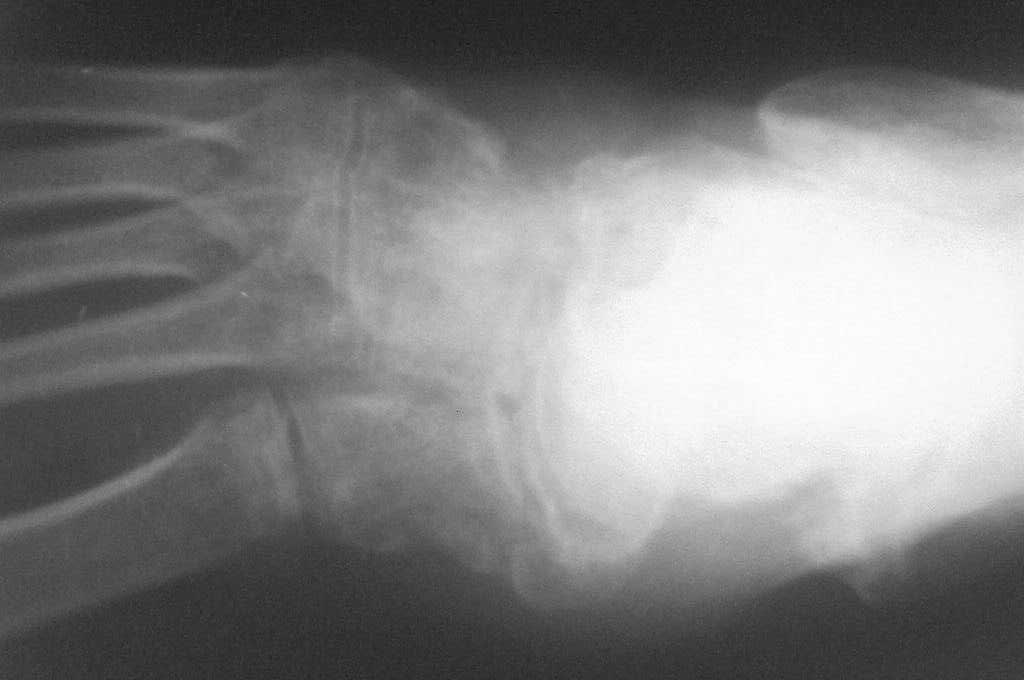

Обратился больной 46 лет. 3 месяца назад получил травму левой стопы в результате ДТП, живет в отдаленный степной зоне, лечился у местного табиба. Ходит при помощи двух костылей, наступая на пятку, на передный отд стопы наступать не может из-за боли, умеренная отечность стопы и деформация в обл. ладьевидной кости, движения в голеностопном суставе в польном обьеме, в средном отд ограничены и болезненны. Уважаемые коллеги, я пока не знаю что делать, помогите, пожалуйста, советами! С уважением Абдурашид.

По данному случаю, оказалось 3 месяца назад было произведена Р-графия в райбольнице, но больной предпочел лечится у табиба. Присылаю первичные снимки.

Да, наш с Вами диагноз, Абдурашид, подтвердился. Я бы предпочёл артродез, фиксация- в самом простом варианте-винтами 3,5 или 4,5 . Отломок послужит аутотрансплантатом. Плюс внешняя иммобилизация. С уважением, Волна